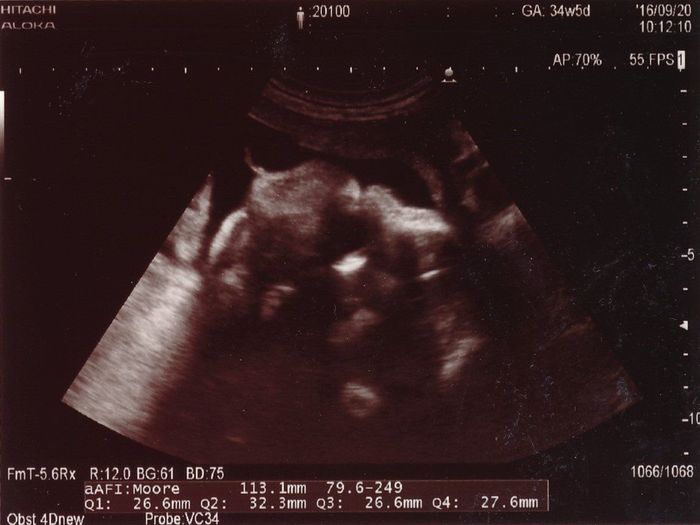

妊娠34週目のエコー写真

赤ちゃんの顔の写真です。左が頭で右があご、中央の黒丸が目で、間の白い部分が鼻です。この頃には帝王切開手術の日取りが決まり(1人目が緊急帝王切開となったため2人目もそうなりました)、とにかく手術日まで無事に過ごすことを考えていました。